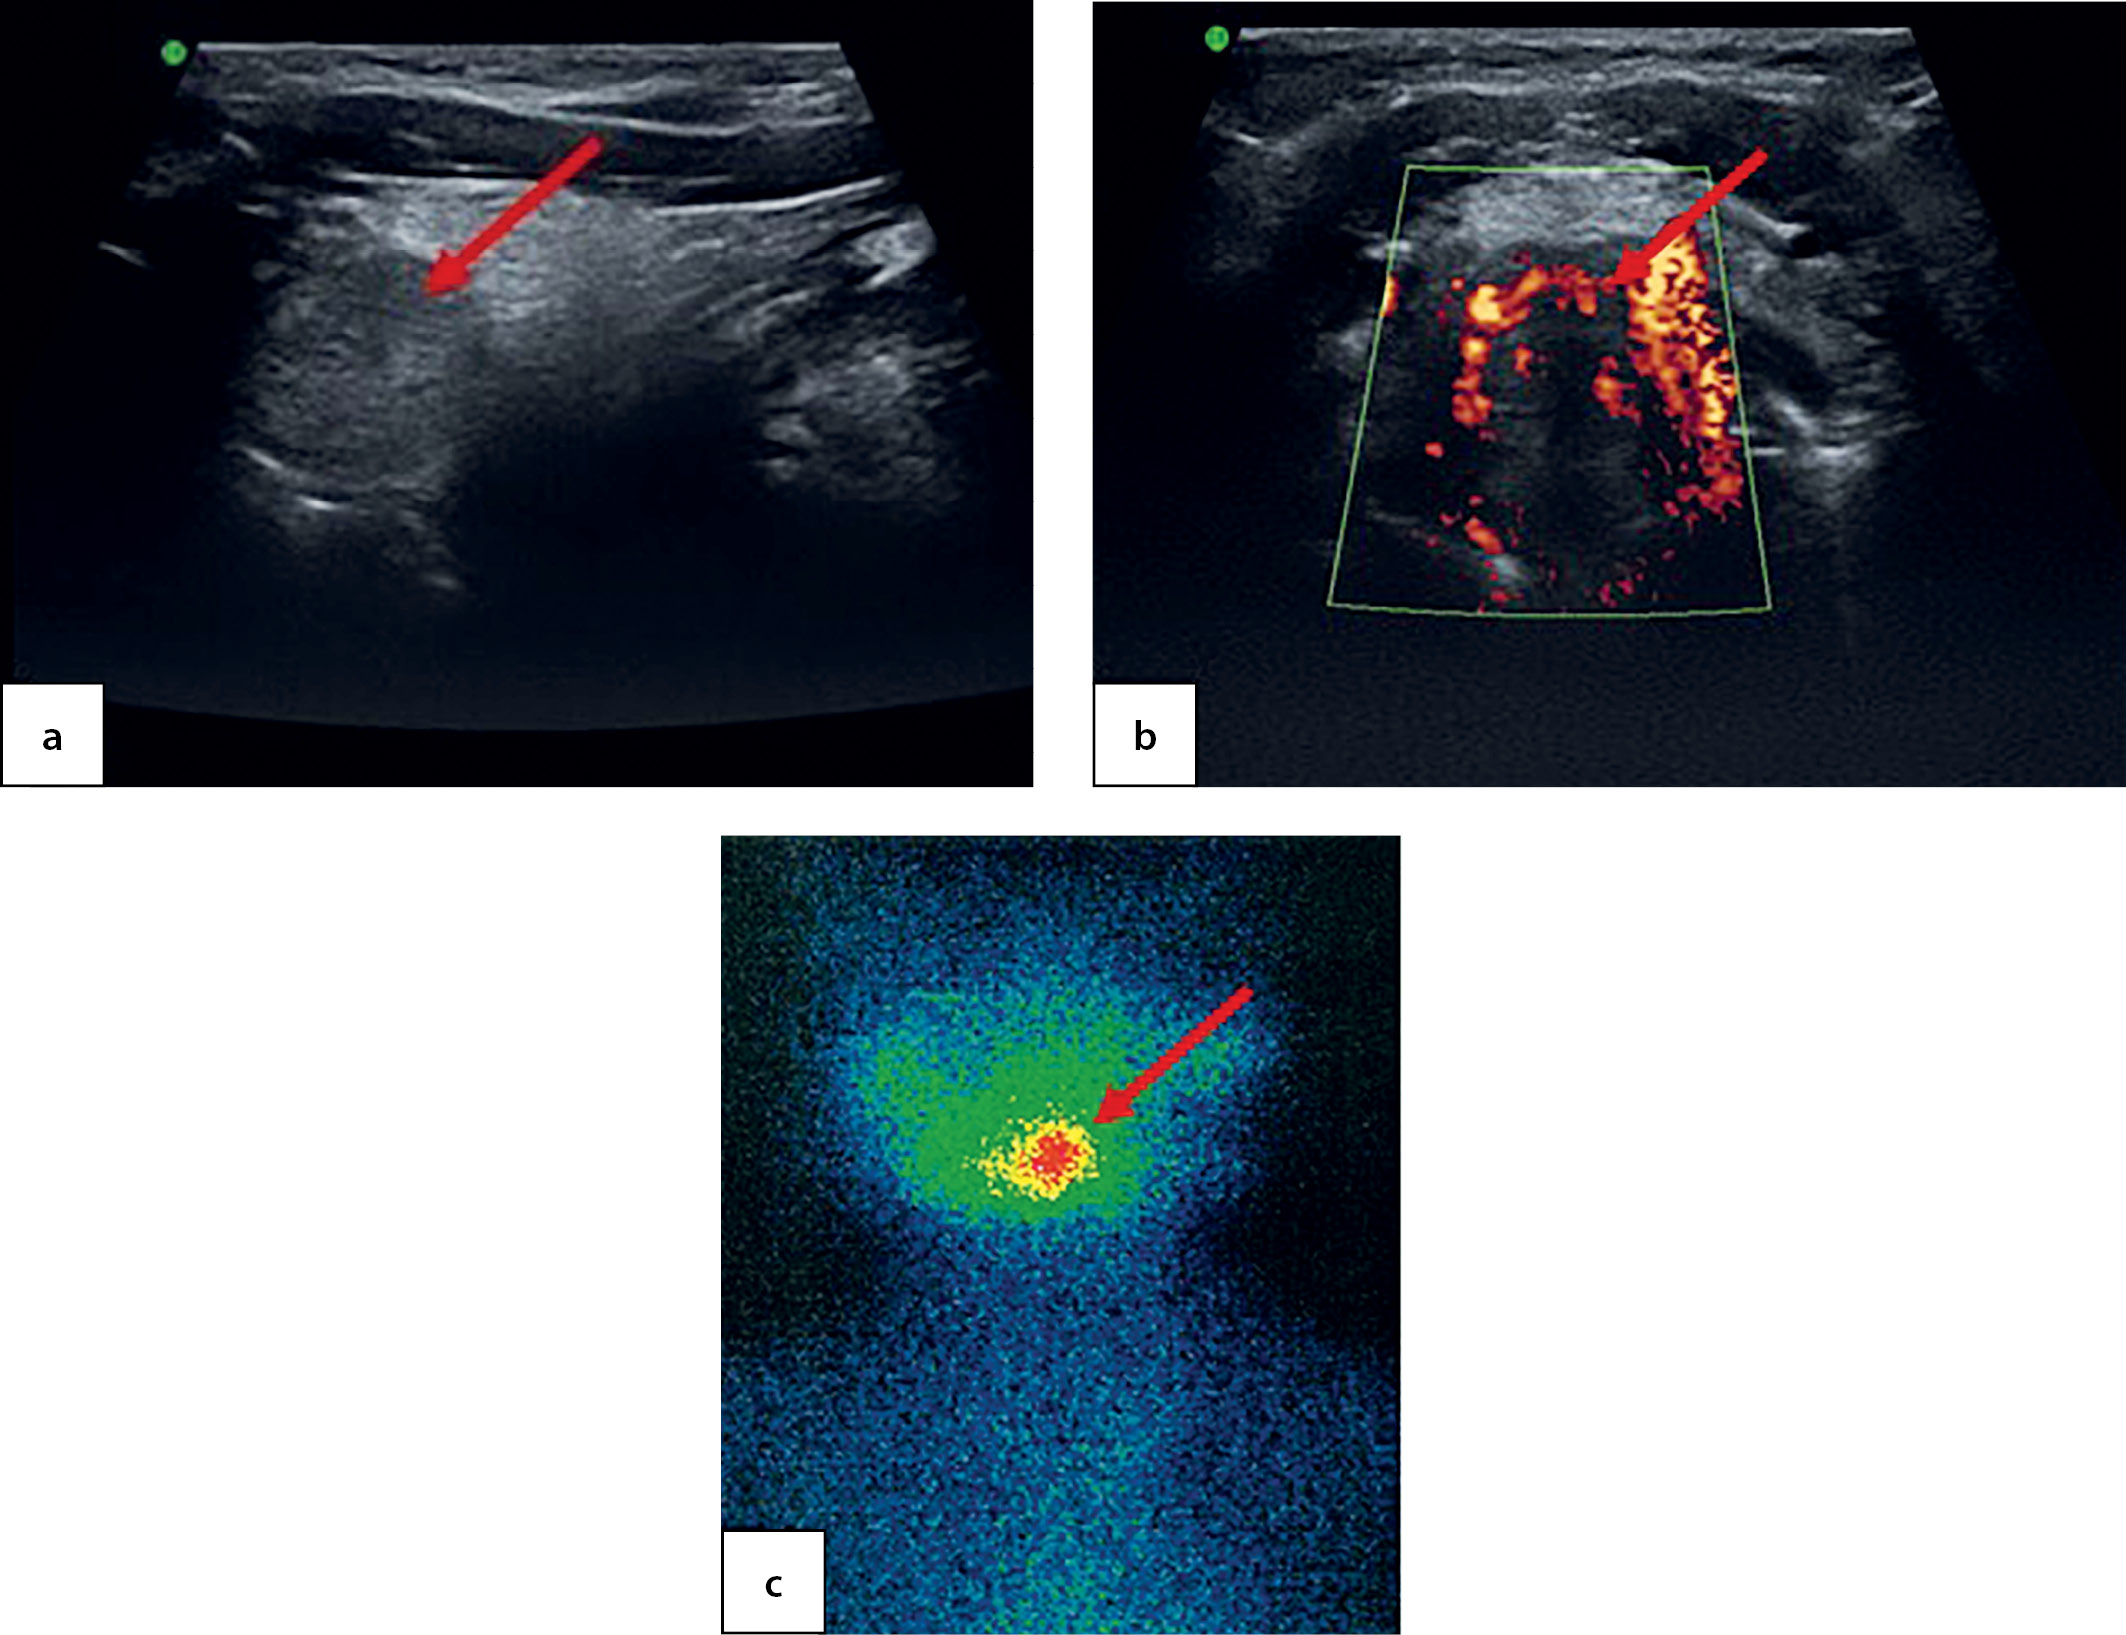

At the age of 7.5 the patient came to the National Endocrinology Research Centre for the first time. An ultrasound imaging found residual thyroid tissue at the root of tongue with dimensions 1.0×0.7×0.5 cm. For the first time, a cyst in the left-hand side of anterior neck was identified with dimensions 0.4×0.3×0.2 cm (Figure 3, a). A thyroid scintiscan confirmed the presence of a round-shaped residual ectopic thyroid tissue 1.4×1.2×1.5 cm in the root of tongue (Figure 3, b). The patient has continued to receive hormone therapy with 2.4 mg/kg/day levothyroxine.

Figure 3. Ectopic thyroid tissue in the root of tongue in a 7.5-year-old patient, as identified through ultrasound imaging (a) and thyroid scintiscan with 99mТc pertechnetate (b)